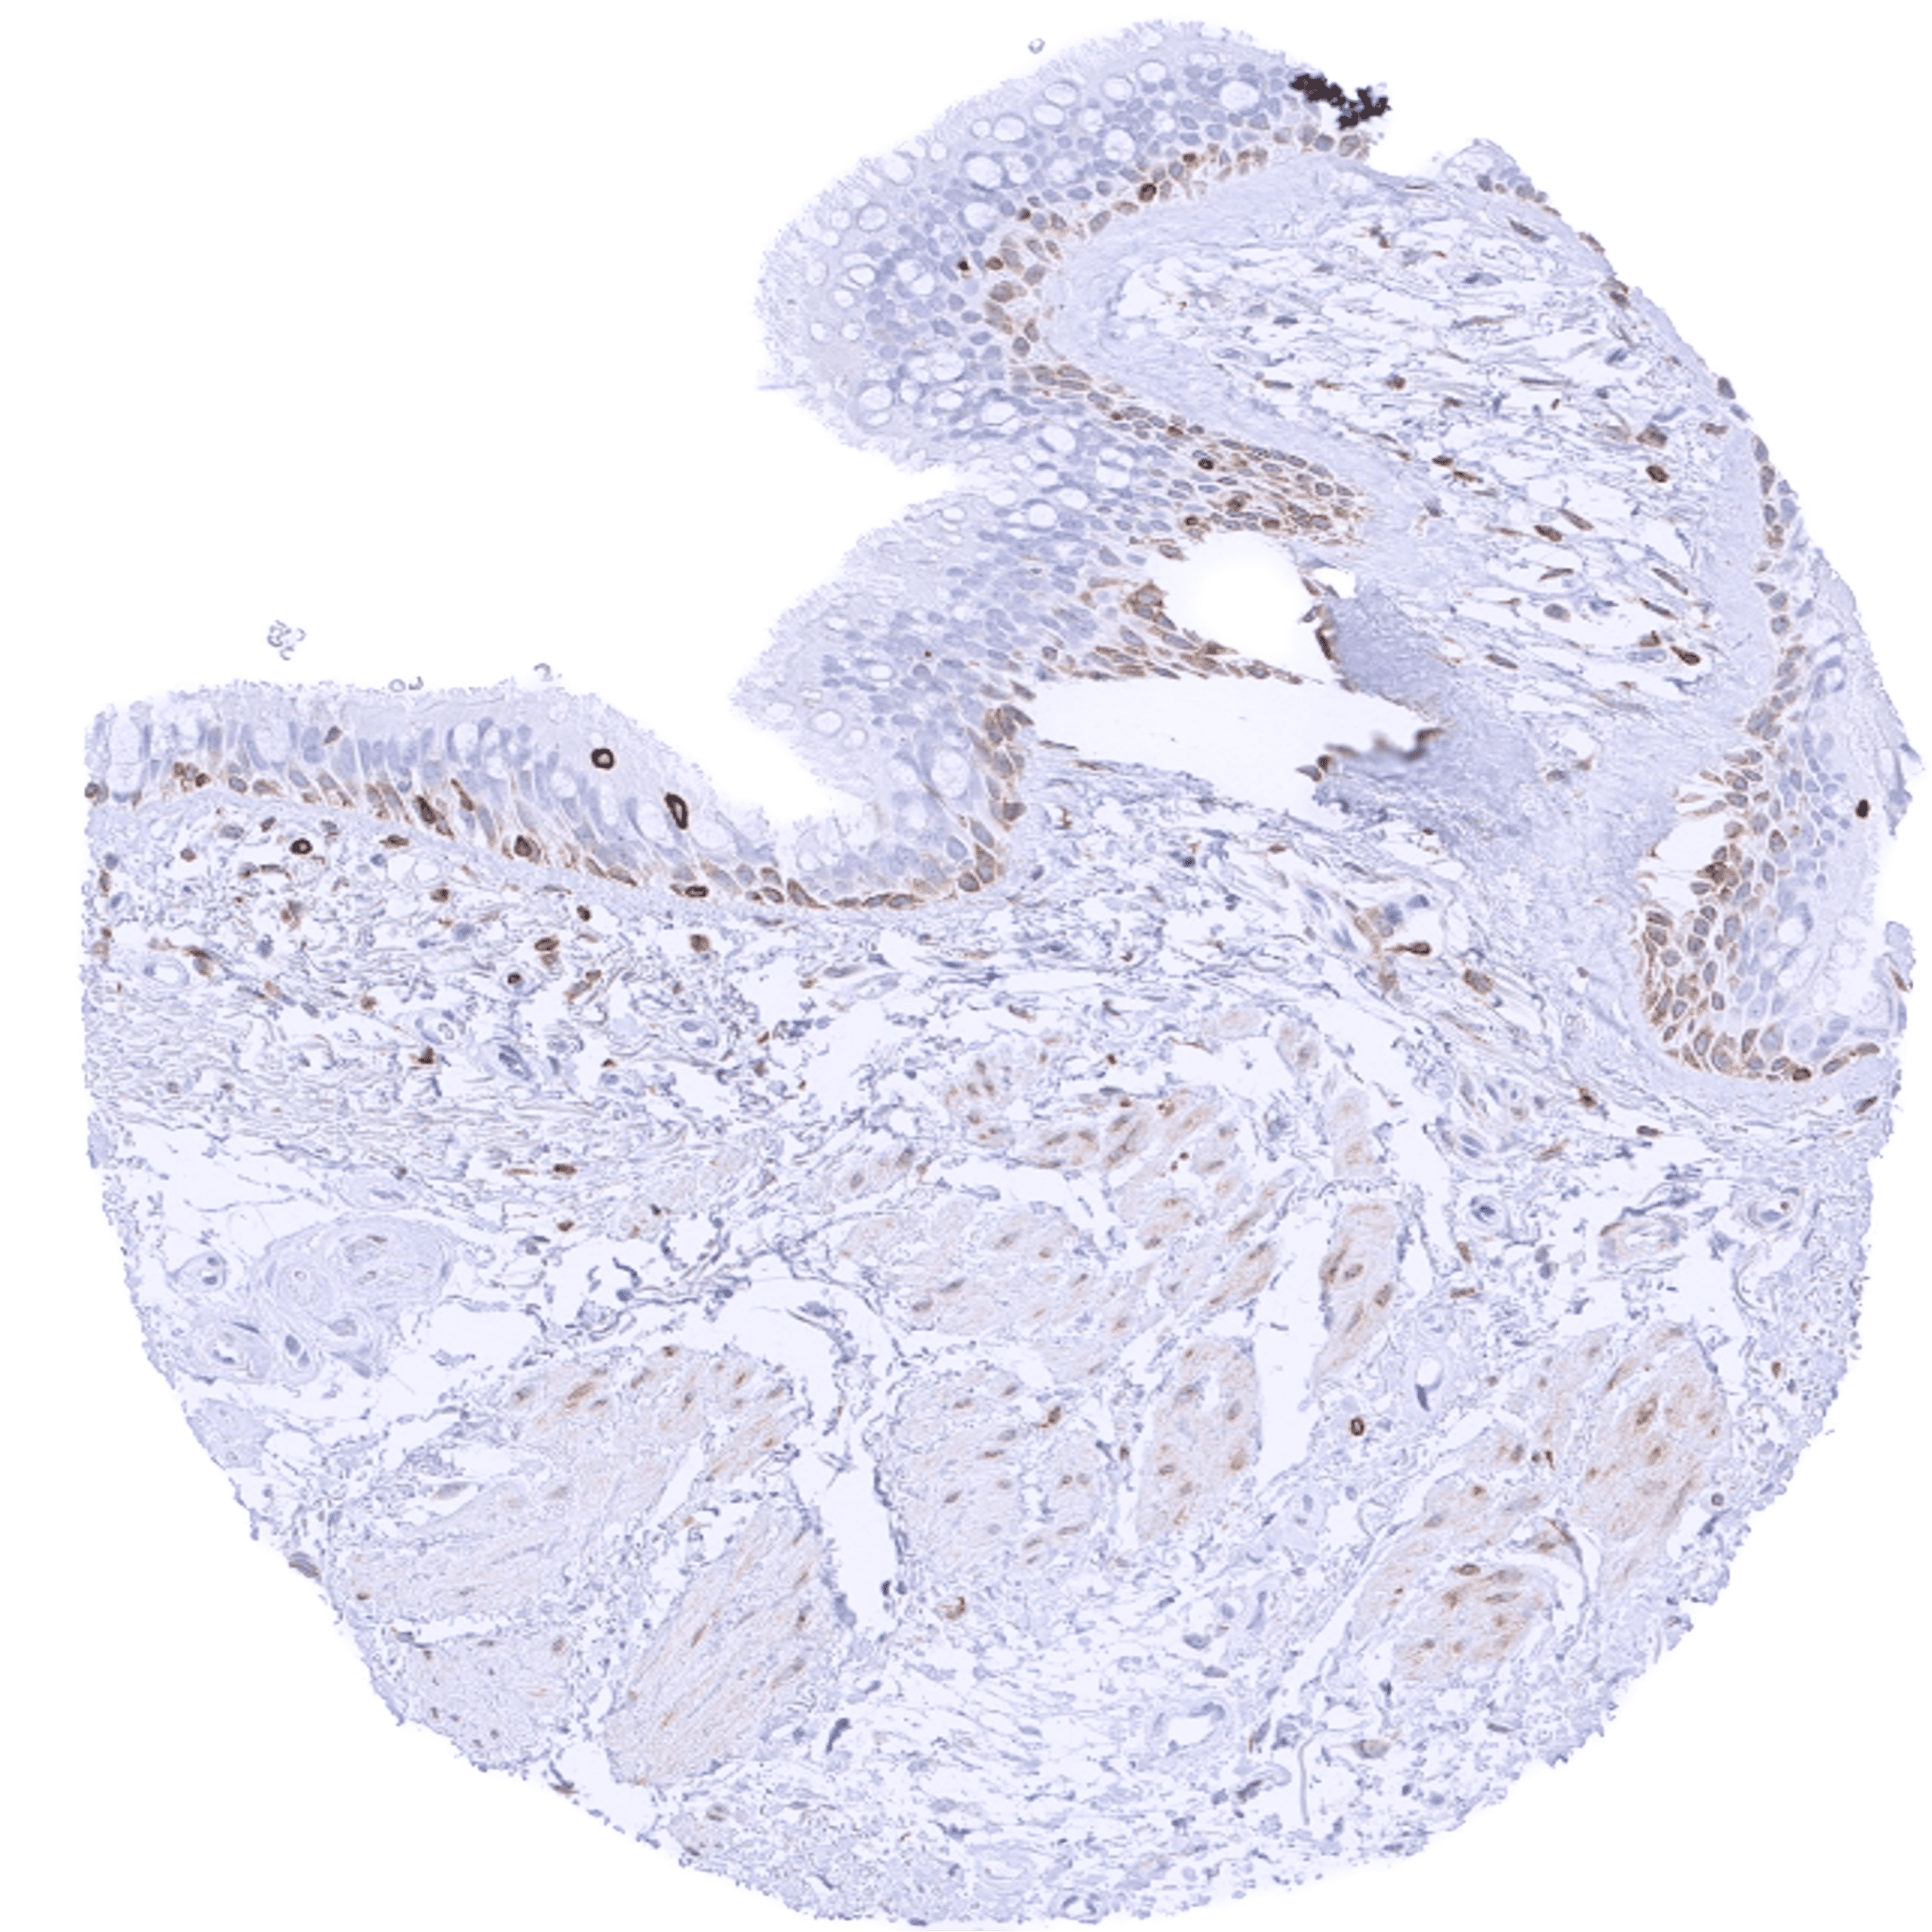

| Uterus, ectocervix | Variable (weak to strong) cytoplasmic bcl-2 staining of basal cells of the squamous epithelium. | |

| Skin | Epidermis | Weak cytoplasmic bcl-2 staining of basal cells of the squamous epithelium. |